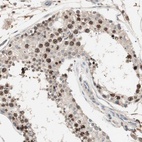

Immunohistochemical staining of human testis shows strong nuclear positivity in cells in seminiferous ducts.